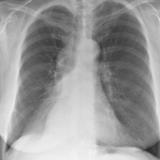

RLL Collapse 1 PA

Date: 02/28/2004

Views: 3496